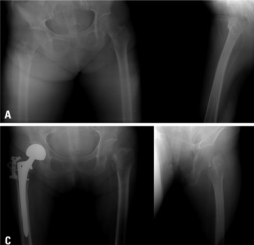

- Compression fractures (~50% post-menopausal women will experience): specifically of the vertebrae, neck of femur/hip

- If affecting vertebrae: note loss of height/khyphosis